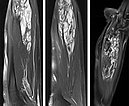

MRI of the forearm in T2-weighted images with spectral fat saturation (left, middle). The characteristically hyperintense, dilated venous convolutes are shown. These lesions enhance contrast medium in the late phase (T1 after contrast; right). The central thromboses appear within these caverns as hypointense areas.

MRI of the forearm (T1 with spectral fat saturation after gadolinium administration) demonstrates almost complete occlusion of the dysplastic veins, which initially thrombosed and then subsequently scarred after sclerotherapy.